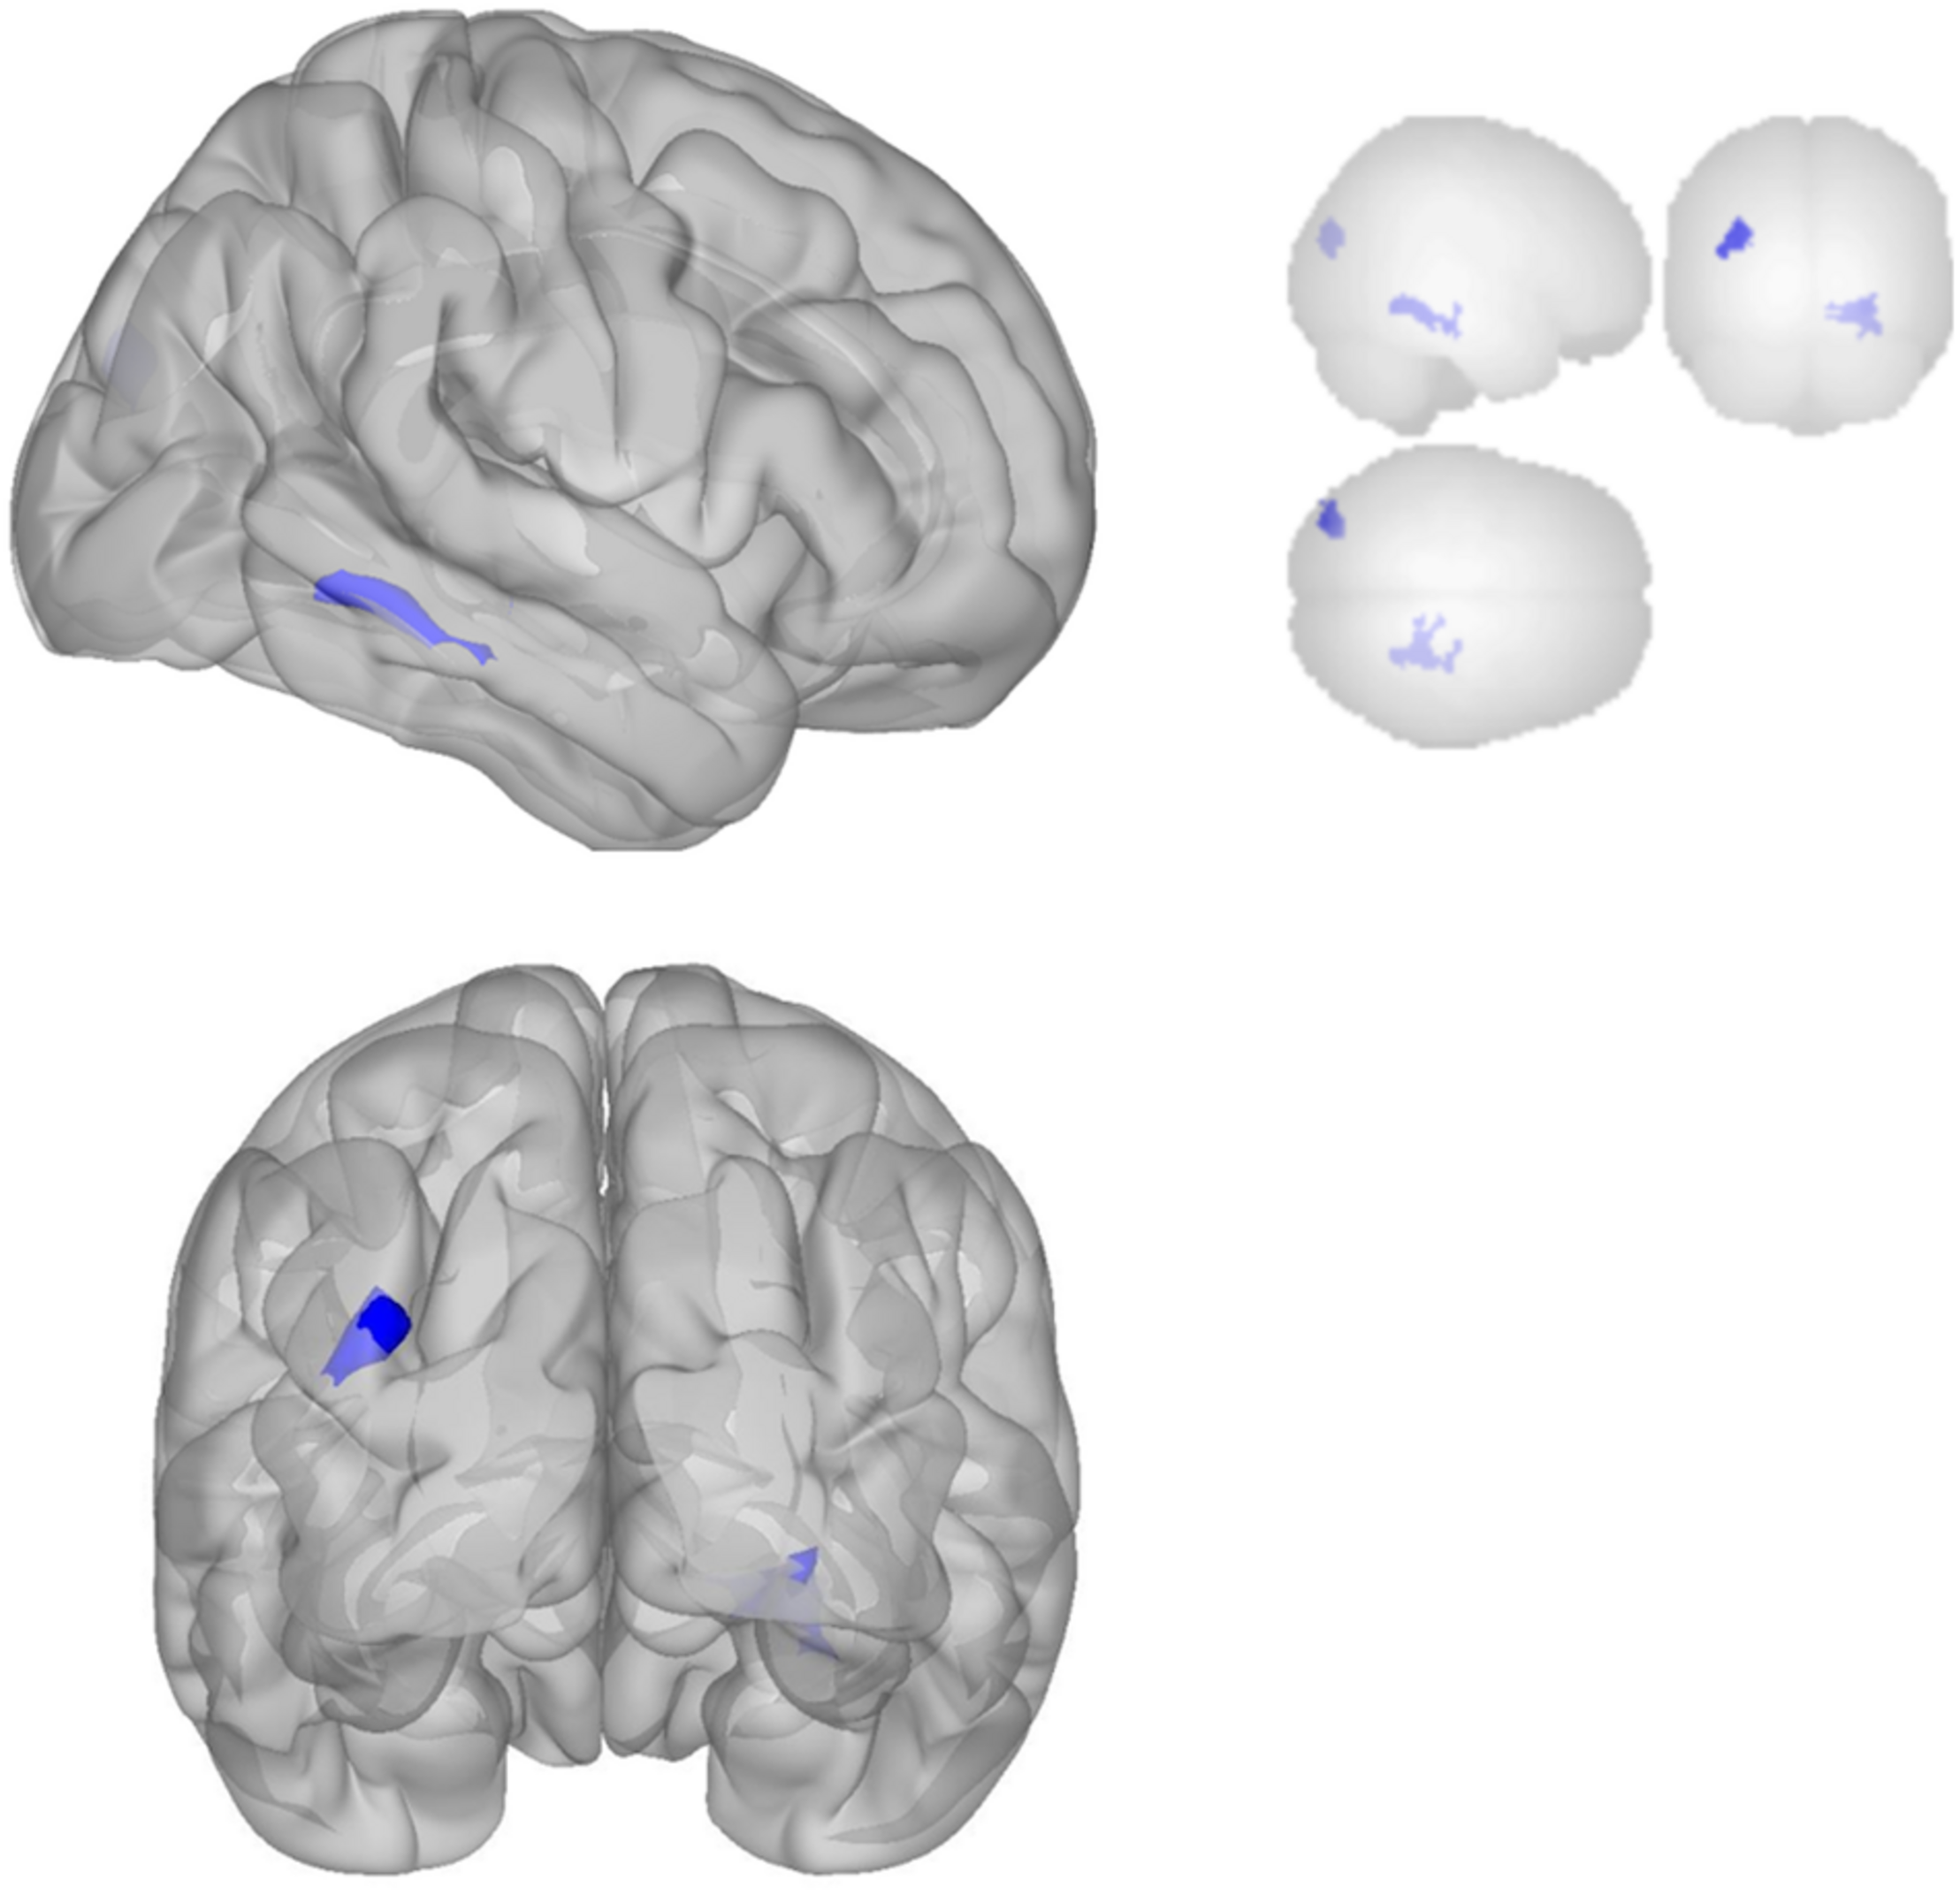

fMRI Connectivity Results

Functional connectivity decreased after sonication within the rIFG network used in the seed-to-voxel analysis. Compared to the baseline, participants had significantly reduced connectivity between the rIFG and the subgenual cortex, orbitofrontal cortex, inferior prefrontal gyrus, dorsal anterior cingulate cortex, and entorhinal cortex (Table 4 and Figure 2). The analysis revealed significant increases in connectivity between the rIFG and the premotor cortex (Table 5 and Figure 2).

FIGURE 2

Significant clusters for the rIFG seed-to-voxel analysis. Increased connectivity with rIFG is shown in red and decreased connectivity with rIFG in blue in the Post-scan relative to Baseline.

The DMN demonstrated decreased connectivity after sonication. For the MPFC seed, there was decreased connectivity with the premotor cortex, and ventral anterior cingulate cortex (Table 4 and Figure 3) and increased connectivity with the superior temporal gyrus, insular cortex, primary auditory cortex, and subcentral area (Table 5 and Figure 3). The PCC seed demonstrated decreased connectivity with the parahippocampal cortex, fusiform gyrus, perirhinal cortex, entorhinal cortex, and associative visual cortex (Table 4 and Figure 4). Figures 2, 3 represent the regions of interest (seeds) and the corresponding locations of clusters of significant difference between pre- and post-sessions.